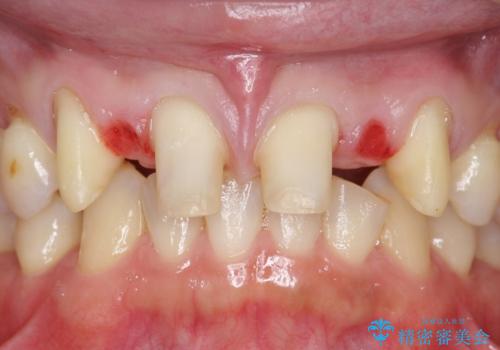

- 前歯部のすきっぱと歯並びが気になるので診て欲しいといらっしゃった方の症例です。

全顎矯正は御希望されなかったため、上顎前歯部のみの部分矯正とオールセラミッククラウンによる補綴を行いました。

- オールセラミッククラウン…¥100,000×6、仮歯…¥10,000×6、部分矯正…¥200,000費用は治療当時の料金となります